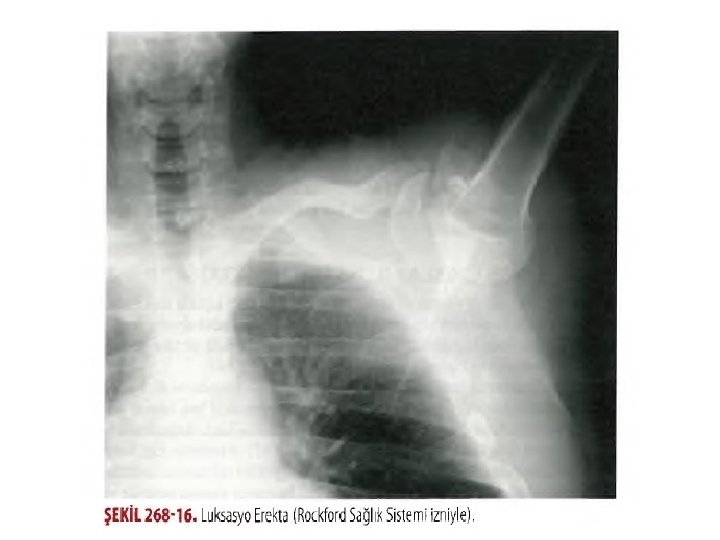

İNFERİYOR CIKIKLAR (LUKSASYO EREKTA) • İnferiyor çıkık ciddi yumuşak doku travması veya bir kırıkla ilişkilidir. • Humerus boynu akromiyonun karşısındayken hiperabduksiyona zorlayan bir güçle karşılaştığı zaman oluşur. İnferior kapsül yırtılır ve humeral baş inferiora doğru hareket eder.

• Hasta, humerus tam abduksiyonda, dirsek fleksiyonda ve el, hastanın başı üzerinde veya arkasında olarak gelir. • Humeral baş lateral göğüs duvarında hissedilebilir. • Yerine takma humerus hattı doğrultusunda yukarı ve dışa doğru uygulanır. • Yardımcı kişi karşı traksiyon uygular. • Yerine takma sonrası kol hastanın yanına getirilir ve omuz sabitleyiciyle sabitlenir.